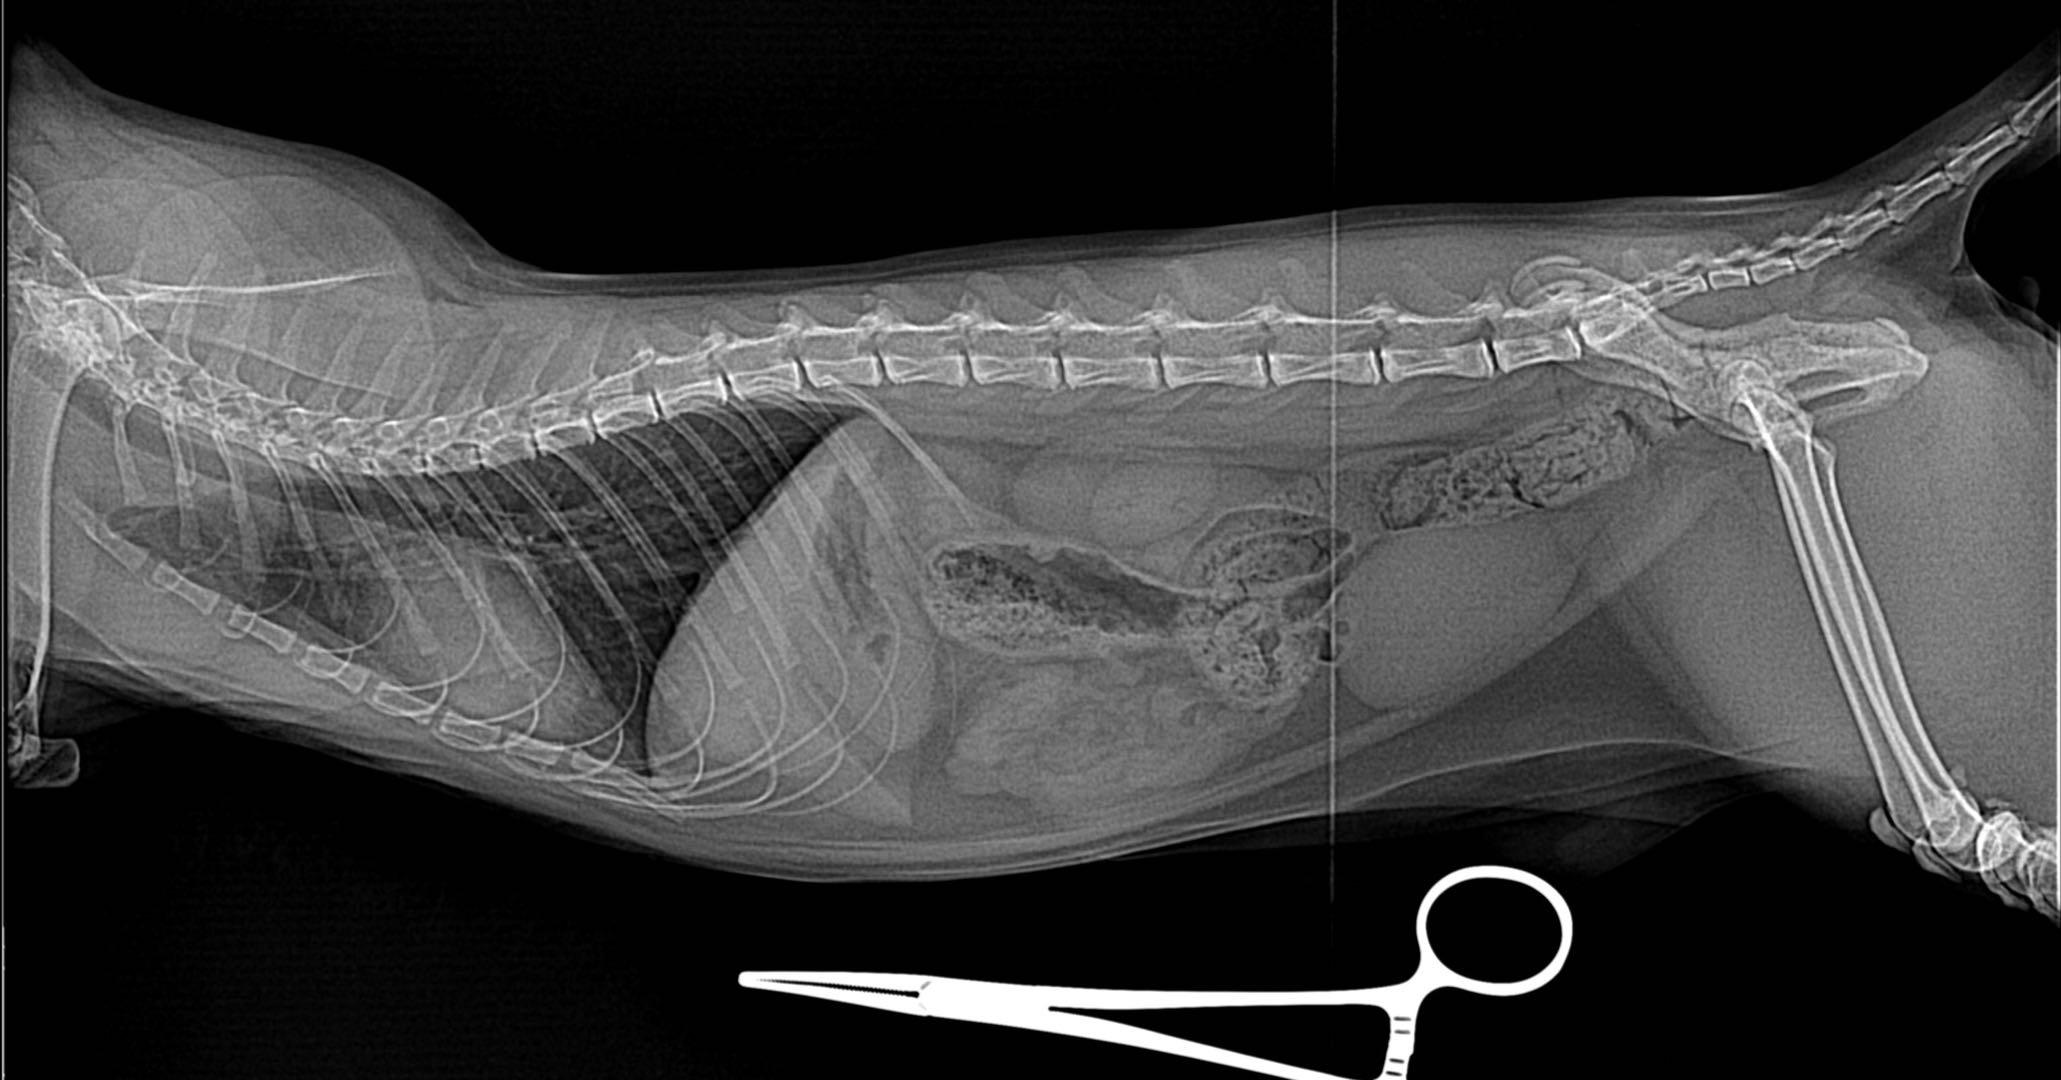

2.影像诊断

影像诊断包括X光以及B超,可以帮助检查膀胱和尿道里面是否有梗阻物或者结石,检查肾脏是否有问题。